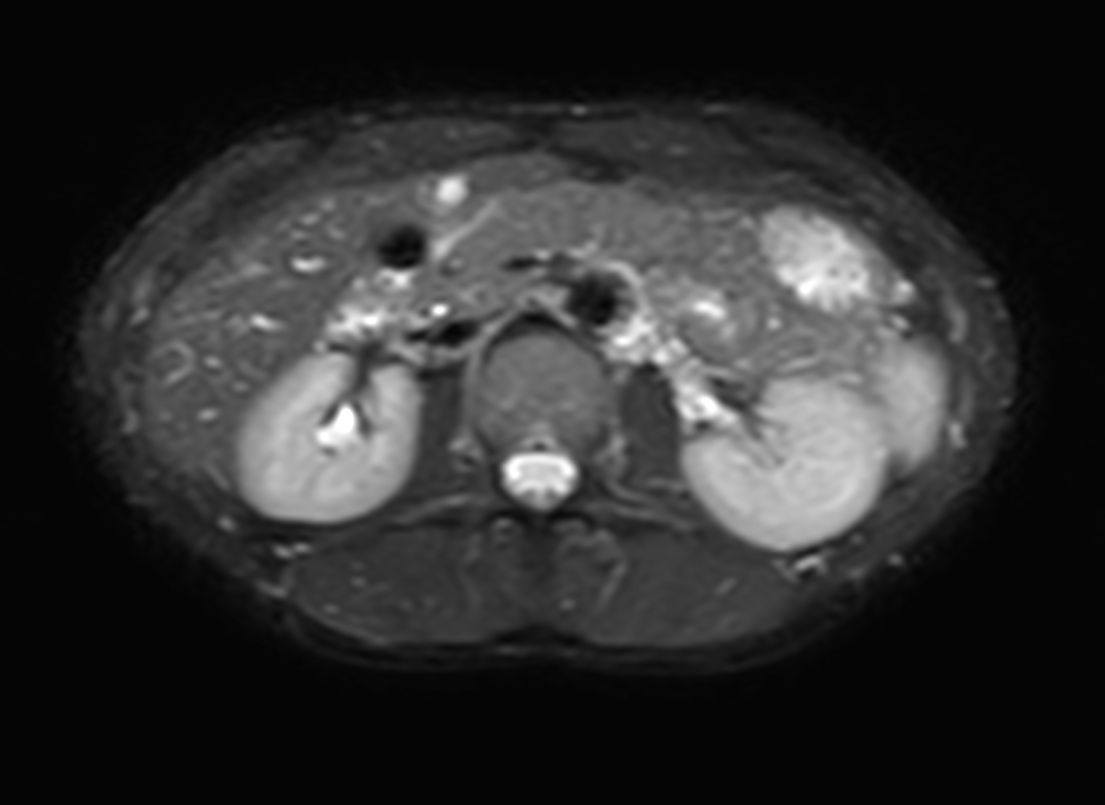

Axial MultiVane XD - T2w SPIR